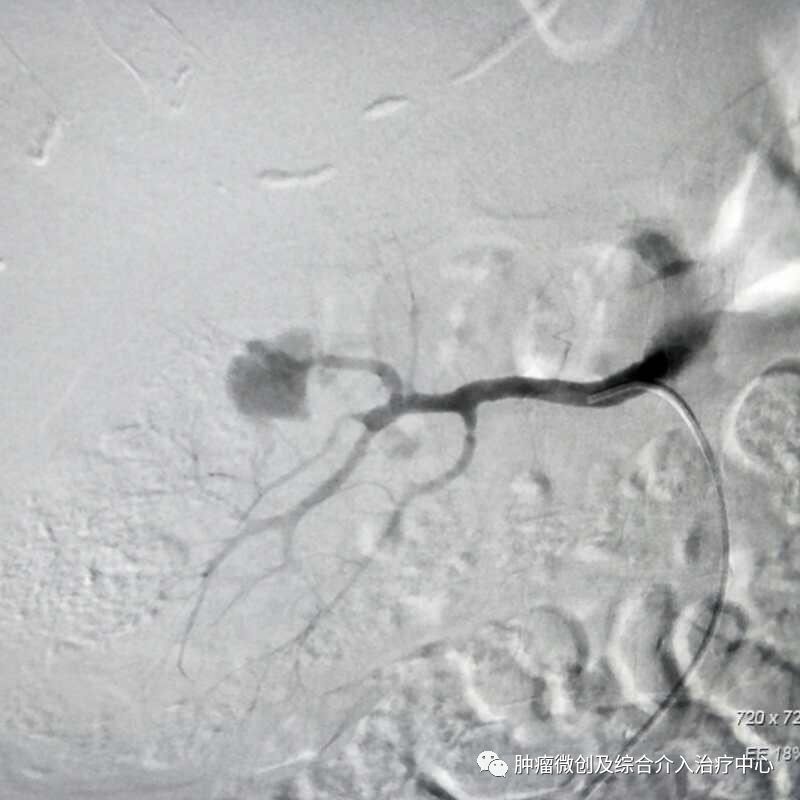

( DSA造影提示胃十二指肠分支血管出血)